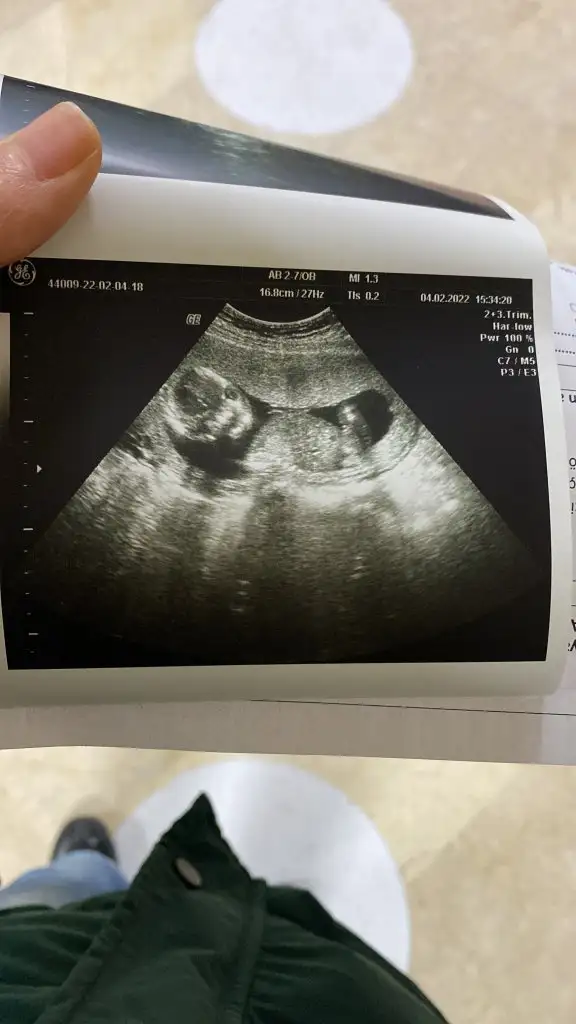

Doktor erkek dedi kizlar. Gönlümden geçen kızdı ama rabbim sağlık sıhhat versin.Canım nubu goruluyormu bilmiyorum ama.sizce ne.

Rabbim sağlık versin inşallahDoktor erkek dedi kizlar. Gönlümden geçen kızdı ama rabbim sağlık sıhhat versin.